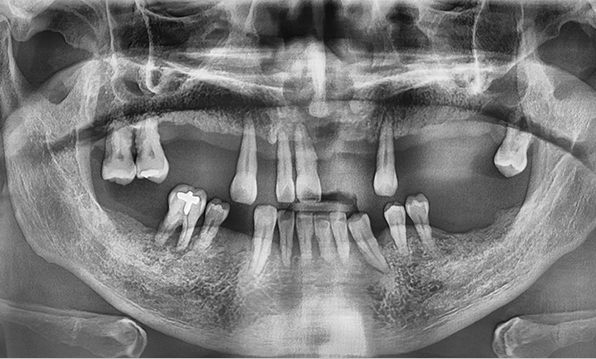

잇몸뼈가 얇은 상태

-

잇몸뼈 충분히 이식 후 임플란트 식립

성공을 위한 노하우, 잇몸뼈 재건 기술

전체 임플란트를 해야하는 환자들은

대부분 고령의 환자들로 오랜 틀니 사용

또는 노화로 인해 치조골이

거의 남아있지 않는 경우가 많습니다.

이 때, 치조골 이식을 병행하여 잇몸뼈 재건 후 안정적인 임플란트 식립을 하고 있습니다.

치료기간 : 2021.04.12~2021.09.15